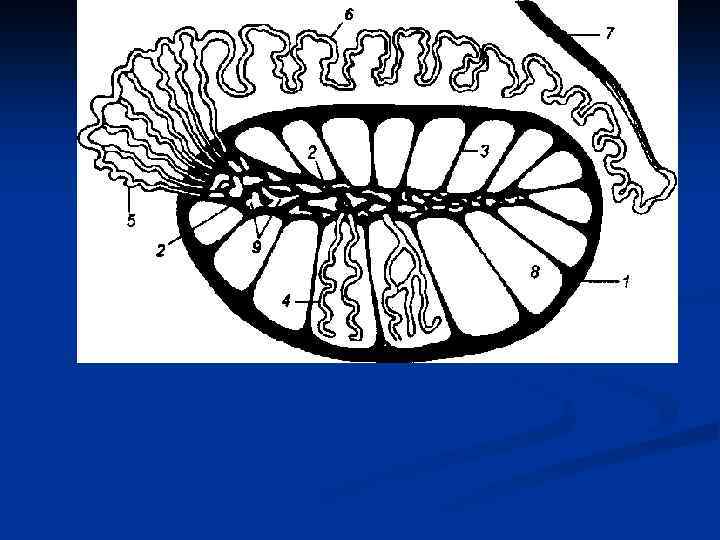

Путь выведения спермы: 1. Извитые семенные канальцы (700 -900) 2. Прямые семенные канальцы (250 -300) 3. Сеть яичка 4. Выносящие канальцы яичка (12 -15) 5. Проток придатка яичка 6. Семявыносящий проток (4 части – яичковая, канатиковая, паховая и тазовая) 7. Ампула семявыносящего протока + выделительный проток семенного пузырька 8. Семявыбрасывающий проток 9. Мужская уретра

Путь выведения спермы: 1. Извитые семенные канальцы (700 -900) 2. Прямые семенные канальцы (250 -300) 3. Сеть яичка 4. Выносящие канальцы яичка (12 -15) 5. Проток придатка яичка 6. Семявыносящий проток (4 части – яичковая, канатиковая, паховая и тазовая) 7. Ампула семявыносящего протока + выделительный проток семенного пузырька 8. Семявыбрасывающий проток 9. Мужская уретра

1. 2. 3. 4. 5. 6. 7. 8. 9. Путь выведения спермы: Извитые семенные канальцы (700 -900) Прямые семенные канальцы (250 -300) Сеть яичка Выносящие канальцы яичка (12 -15) Проток придатка яичка Семявыносящий проток (4 части – яичковая, канатиковая, паховая и тазовая) Ампула семявыносящего протока + выделительный проток семенного пузырька Семявыбрасывающий проток Мужская уретра

1. 2. 3. 4. 5. 6. 7. 8. 9. Путь выведения спермы: Извитые семенные канальцы (700 -900) Прямые семенные канальцы (250 -300) Сеть яичка Выносящие канальцы яичка (12 -15) Проток придатка яичка Семявыносящий проток (4 части – яичковая, канатиковая, паховая и тазовая) Ампула семявыносящего протока + выделительный проток семенного пузырька Семявыбрасывающий проток Мужская уретра